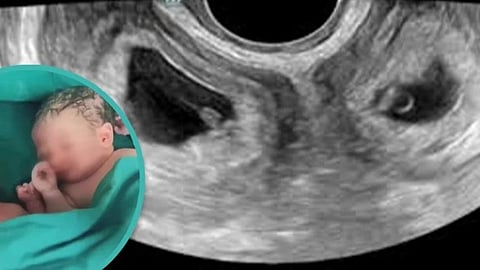

சீனாவில் 2 கருப்பைகளைக்கொண்ட பெண் ஒருவர், இரண்டு கருப்பையிலிருந்தும் தலா ஒரு குழந்தை என மொத்தம் இரண்டு குழந்தைகளை பெற்றெடுத்திருப்பது மருத்துவ உலகின் கவனத்தை பெற்றுள்ளது.

சவுத் சைனா மார்னிங் போஸ்ட்யின்படி, சீனாவின் வடமேற்கு பகுதியை சேர்ந்தவர் லி என்ற பெண்.. இவருக்கு கடந்த செப்டம்பர் மாதம் ஷாங்கி மாகாணத்தில் உள்ள மருத்துவமனையில் இரட்டை குழந்தைகள் பிறந்துள்ளது. குழந்தை பிறந்தது சிறப்பு என்றால், அதிலும் சிறப்பு இப்பெண்ணுக்கு இரண்டு கருப்பையிலிருந்து குழந்தைகள் பிறந்துள்ளது என்பதுதான்.

இதன்படி, லிக்கு முழுமையாக வளர்ச்சி அடைந்த இரண்டு கற்பபைகள் இருந்துள்ளது. இந்த இரண்டு கற்பபைகளிலும் தலா ஒரு குழந்தை என மொத்தம் இரண்டு குழந்தைகள் வளர்ந்து வந்துள்ளது.. இந்தநிலையில்தான், சுகப்பிரசவ முறையிலேயே இவருக்கு இரண்டு கருப்பையிலிருந்து ஒரு ஆண் ஒரு பெண் என இரண்டு குழந்தைகள் பிறந்துள்ளது.